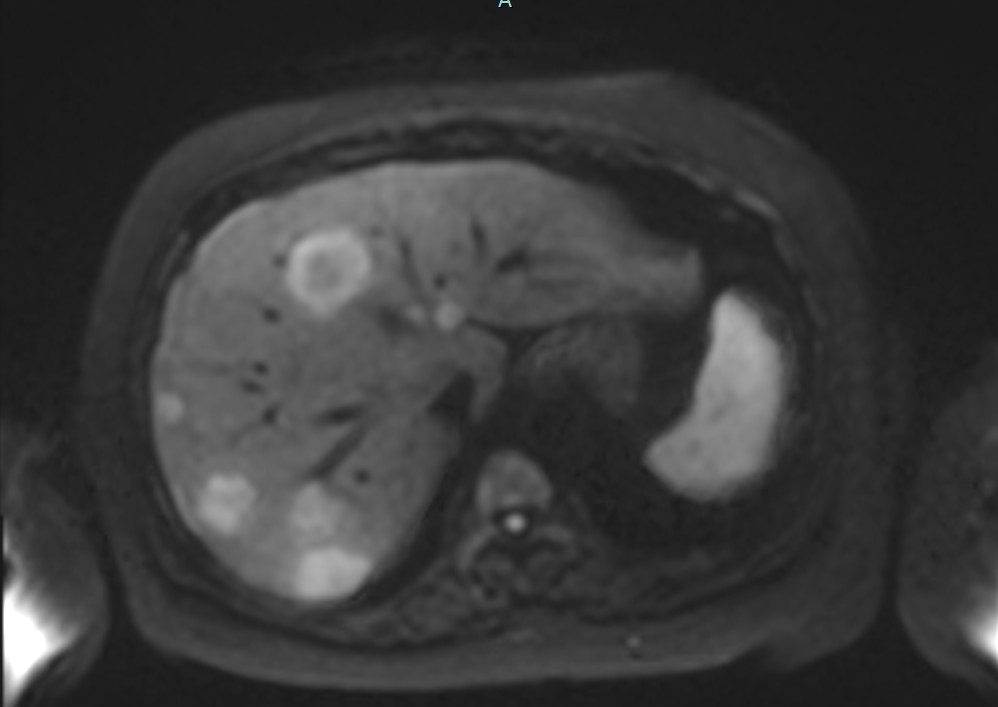

Figure2c. Axial DWI at b=1000 s/mm² showing similar lesion detection with slightly reduced signal intensity compared to b=800.